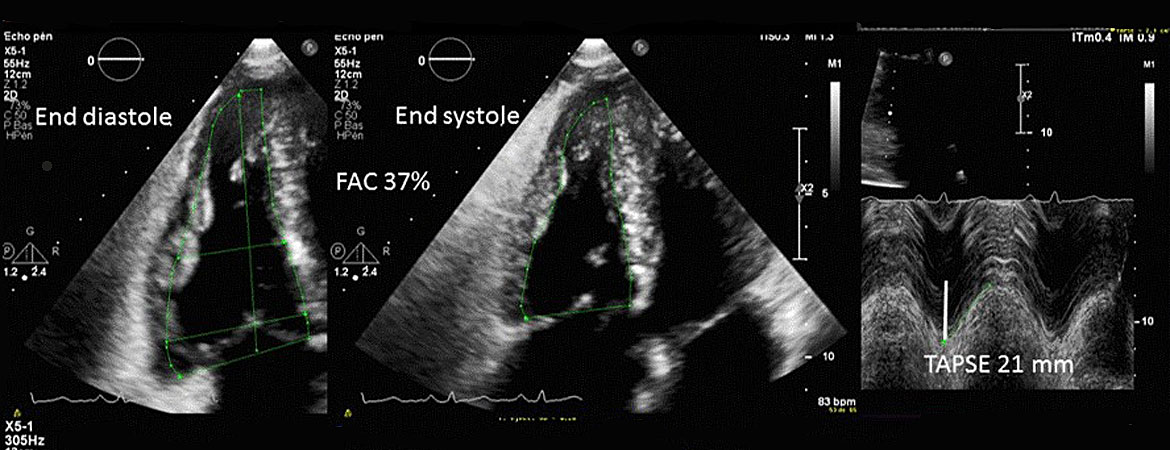

Nicolas Brugger, Mona Lichtblau, Micha T. Maeder, Hajo Müller, Cyril Pellaton, Patrick Yerly (Author) Two-dimensional transthoracic echocardiography at rest for the diagnosis, screening and management of pulmonary hypertension Fulltext PDF Fulltext HTML